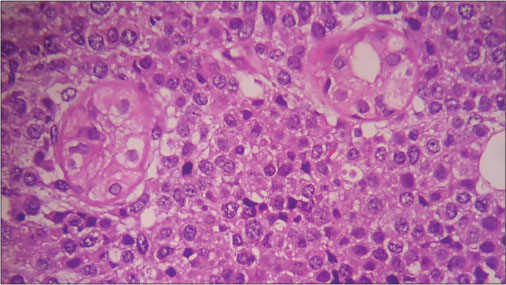

A punch biopsy of the lesion revealed myelomatous plasma cells in the dermis and deep dermis confirming cutaneous involvement [Figure 2] and [3].

|?Figure. 2? Biopsy from the lesion ?10 power

|?Figure. 3? Infiltrating plasma cells ?100